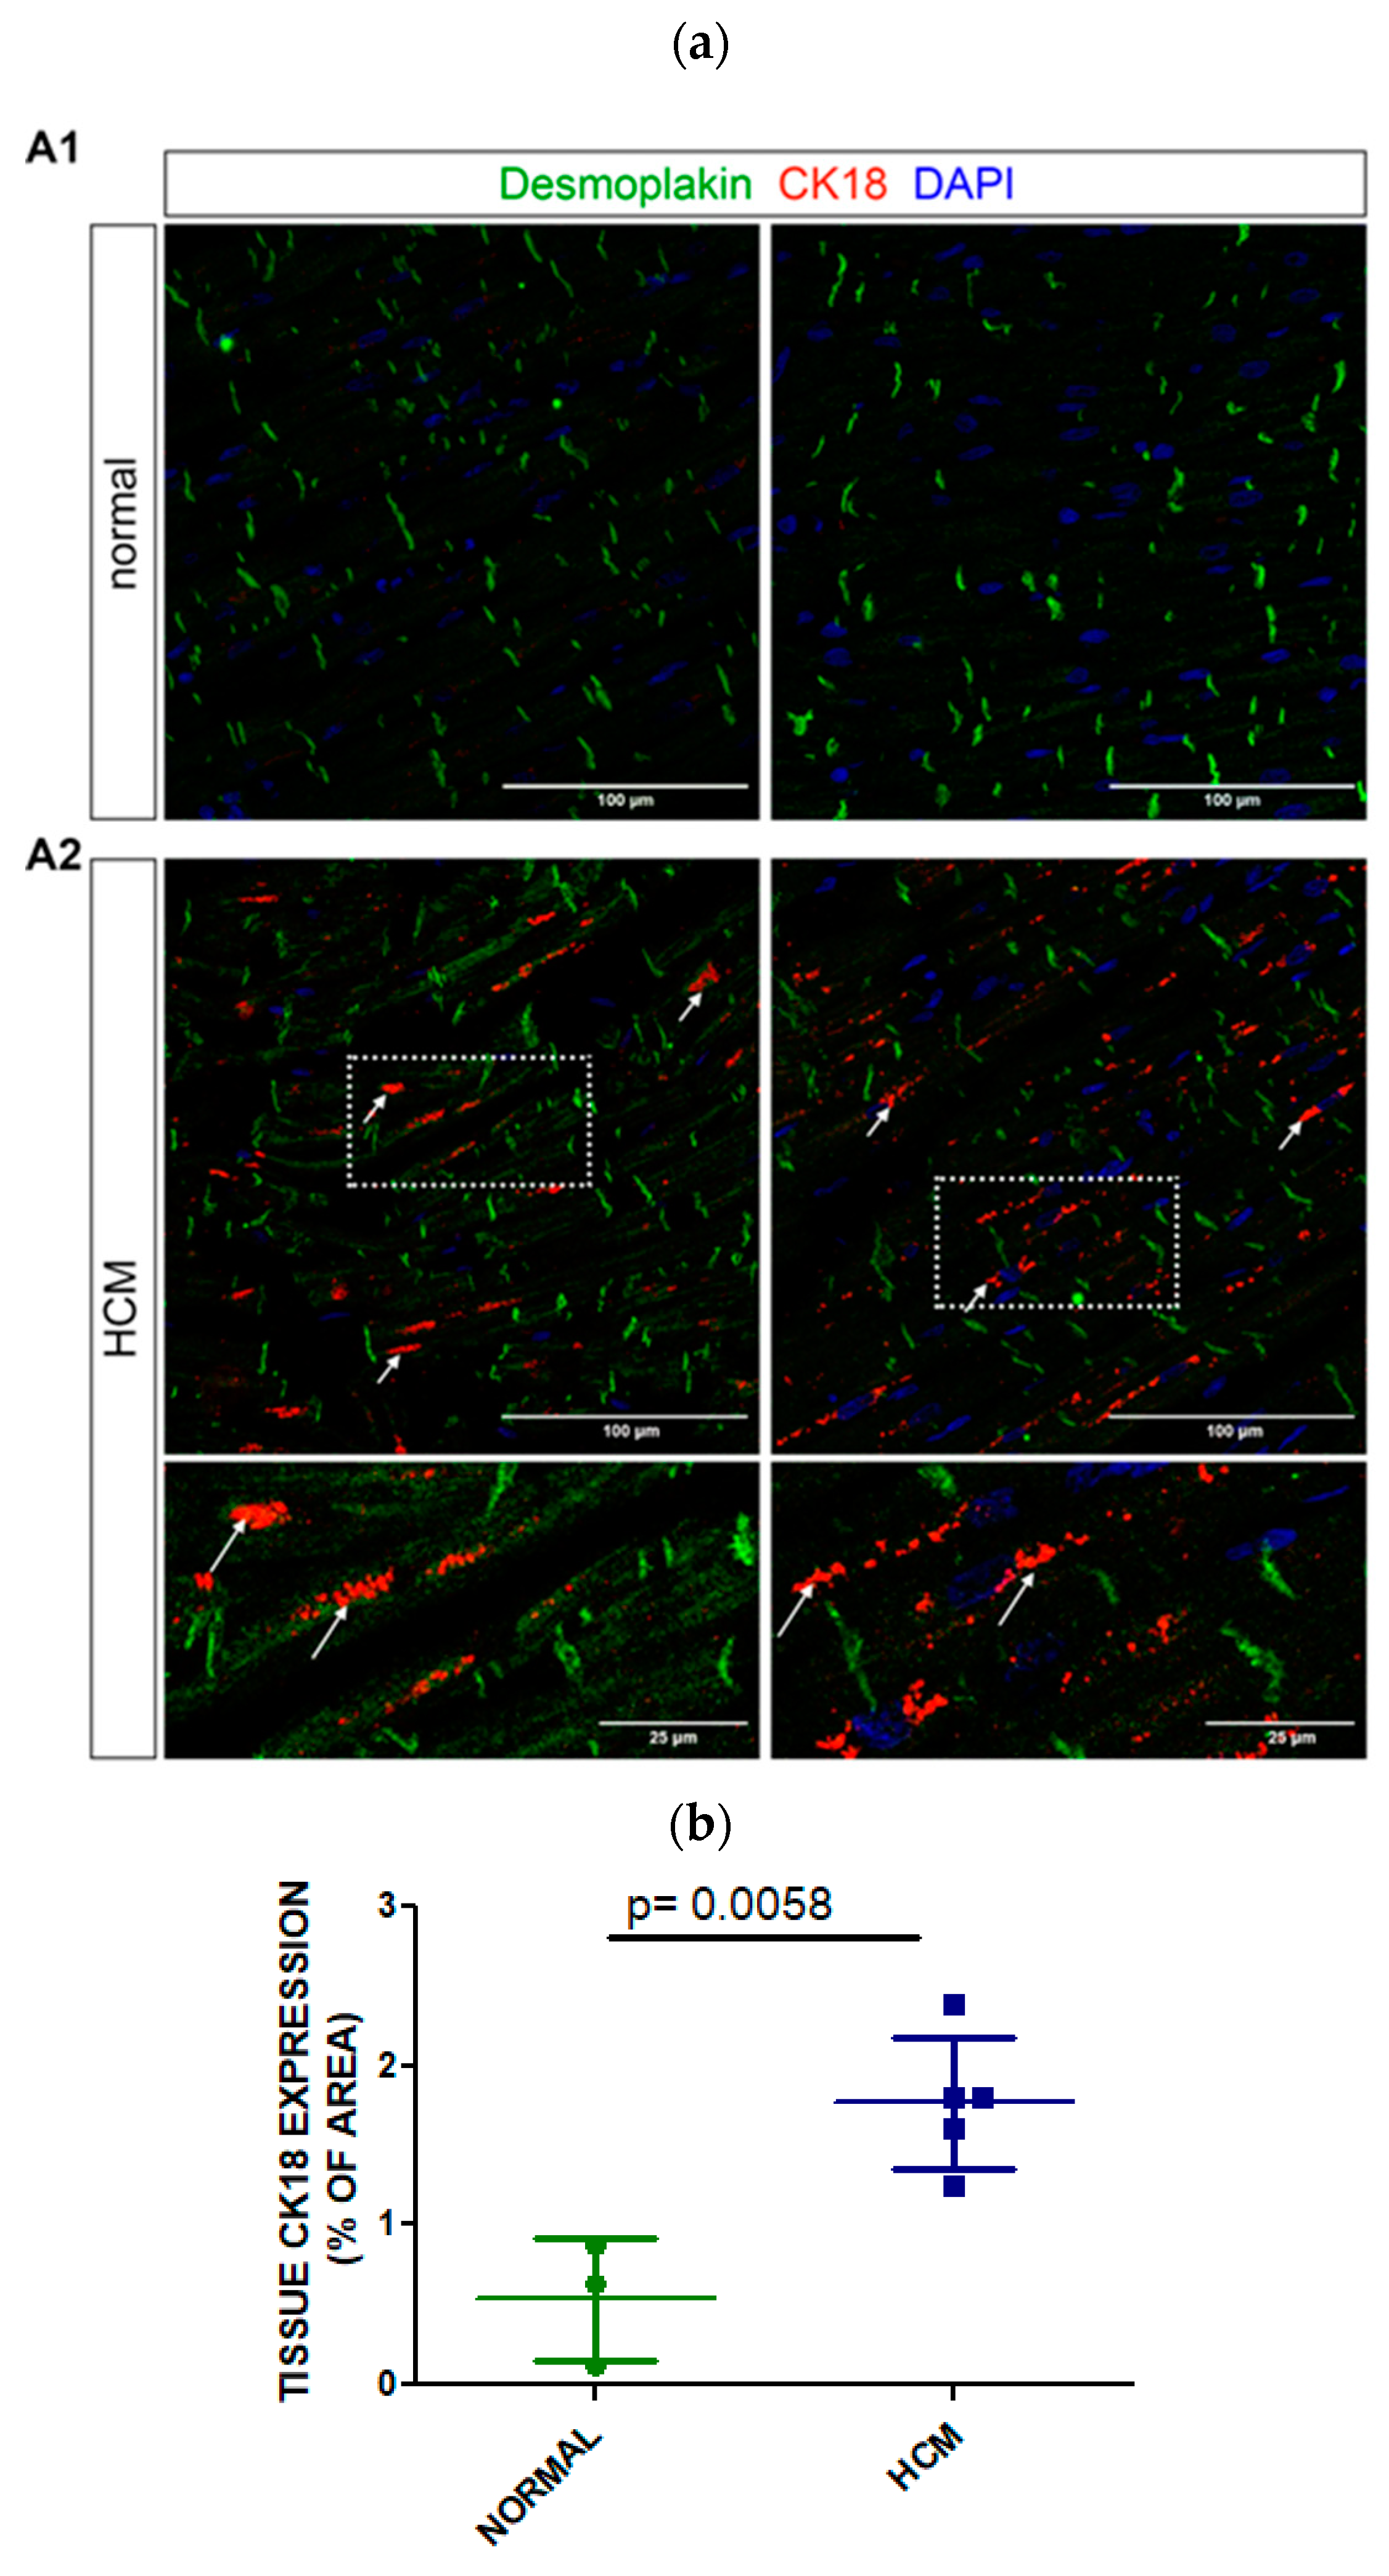

3.4. Tissue Expression of CK18 in Postmortem Myocardial Specimens from an HCM or a Normal Heart